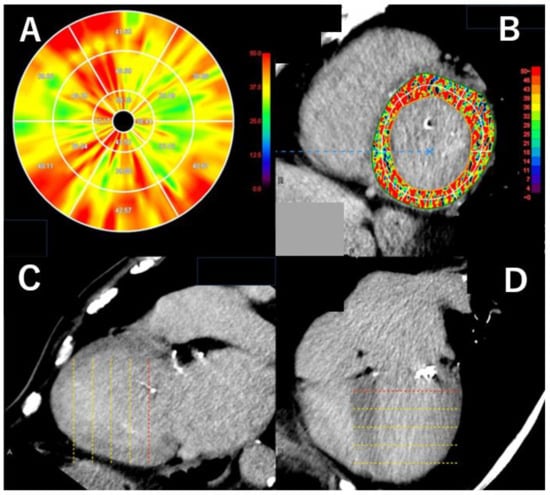

3.5. The Analysis of Myocardial Damage on Computed Tomography

- Andreini, D.; Conte, E.; Mushtaq, S.; Melotti, E.; Gigante, C.; Mancini, M.E.; Guglielmo, M.; Lo Russo, G.; Baggiano, A.; Annoni, A.; et al. Comprehensive Evaluation of Left Ventricle Dysfunction by a New Computed Tomography Scanner: The E-PLURIBUS Study. J. Am. Coll. Cardiol. Imaging 2023, 16, 175–188. [Google Scholar] [CrossRef]

- Aoki, S.; Takaoka, H.; Ota, J.; Kanaeda, T.; Sakai, T.; Matsumoto, K.; Noguchi, Y.; Nishikawa, Y.; Yashima, S.; Suzuki, K.; et al. Strong Diagnostic Performance of Single Energy 256-row Multidetector Computed Tomography with Deep Learning Image Reconstruction in the Assessment of Myocardial Fibrosis. Intern. Med. 2024, 63, 2499–2507. [Google Scholar] [CrossRef]